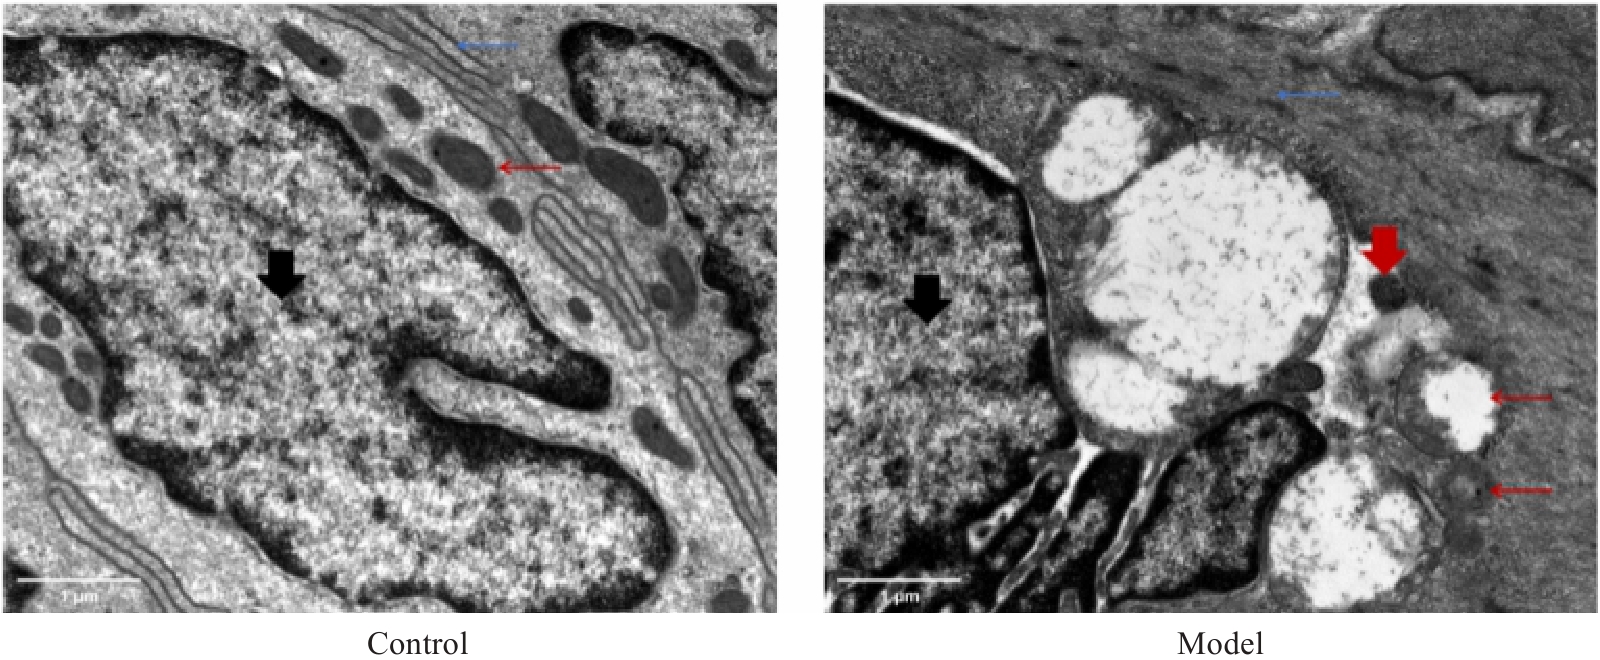

图1 化瘀通便汤对STC大鼠结肠ICCs超微结构的影响

Fig.1 Effect of Huayu Tongbian Decoction on ultrastructure of interstitial Cajal cells (ICCs) in the colon tissues of rat models of slow transit constipation (STC) (Original magnification: ×20 000). The black arrow indicates the nucleus, the red thin arrow indicates the mitochondria, the red thick arrow the lysosome, and the blue thin arrow the endoplasmic reticulum.